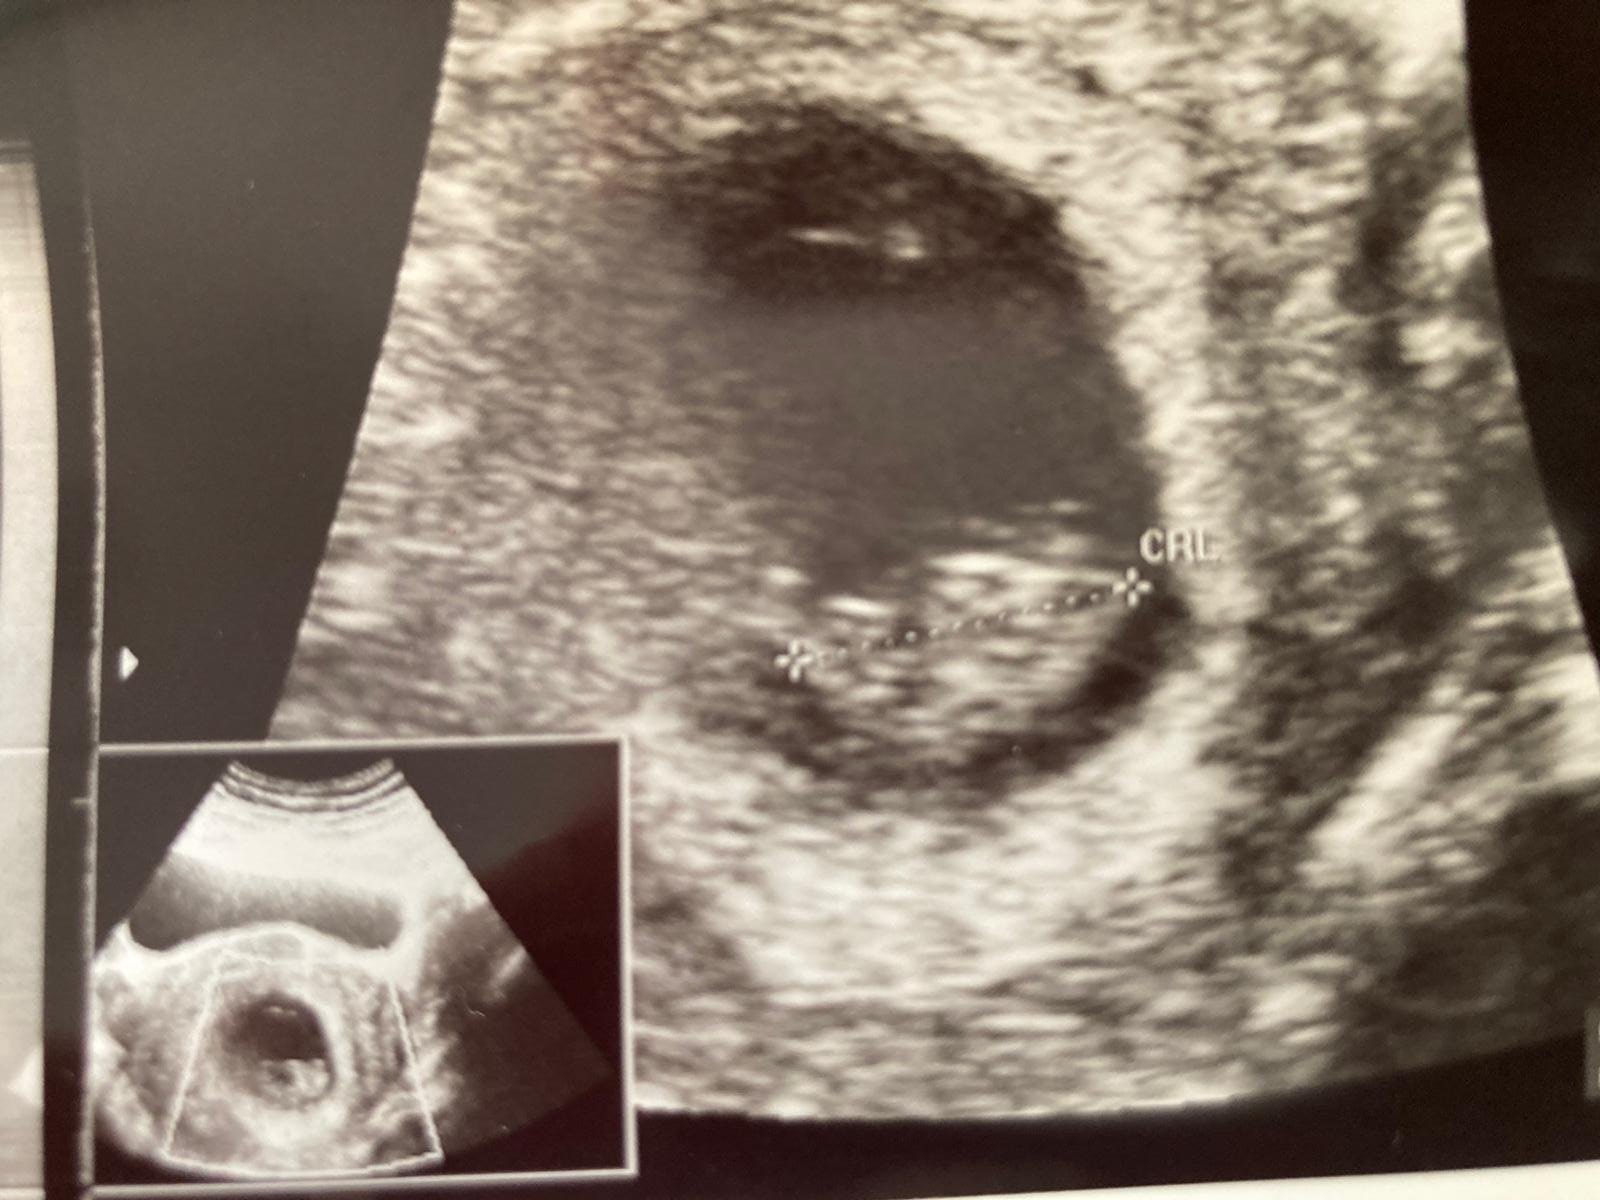

Yok bi tanem bu küçük sıpagettinin cinsiyetini çok net göremiyorum. Hem takılma bunlara sen. Çok net görsek te, vereceğimiz bilgi net değil 🙂 Kız gibi gördük öyle dursun bakalım güzelleşsin serpilsin net görüntü elbet gelecektir. Rabbim sen ve senin gibi anne olmak üzere olanların gönlündekini nasip etsin inşAllah 🙂